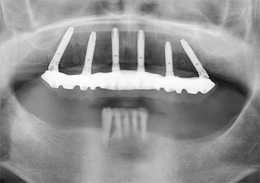

ALL-ON-4(オールオンフォー)の症例写真

上顎のALL-ON-4(ノーベルクリニシャンを使用したフラップレス術式)

- 治療内容

- 上顎に残存していた歯を抜歯。歯肉の治癒後にフラップレス手術にてインプラント埋入を行い、その場で準備してあった上顎上部構造を仮歯として、ねじ固定式で装着

- 治療費用

- 上顎ALL-ON-4:4,000,000円(税別)

- 治療期間

- 6ヶ月